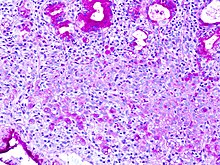

Die PAS-Reaktion (Abk. für engl. periodic acid–Schiff reaction) oder inkorrekt PAS-Färbung ist eine häufig eingesetzte Färbetechnik in der Histologie. Es kommt dabei zur Anfärbung von Kohlenhydraten wie Glykogen, Cellulose, neutralen Mukopolysacchariden, Muko- und Glykoproteinen sowie Glykolipiden. Diese Substanzen sind beispielsweise in Bindegewebsfasern (Kollagen), Basalmembranen, Zellwänden (Glykokalix) und in neutralen Schleimen (Magenschleim) zu finden. Glykogenreiche Zellen findet man z.B. in der Leber und in Muskelgewebe. In der Dermatologie dient sie zum Nachweis PAS-positiver Mikroorganismen (Pilze) als Krankheitserreger in der Haut.

Durch die Periodsäure, ein starkes Oxidationsmittel, werden unsubstituierte Glycolgruppen zu zwei benachbarten Aldehydgruppen oxidiert. Das Schiffsche Reagenz enthält Fuchsinschweflige Säure (farblos). Durch Bindung an die Aldehydgruppen kommt es zu einem molekularen Umbau und die chromogene Eigenschaft entsteht – deutlich erkennbar an der magentaroten Farbe. Im nachfolgenden Schritt wird überschüssige fuchsinschwefelige Säure durch die Sulfitspülung differenziert, entfernt und die Farbe stabilisiert. Als kontrastreiche Kernfärbung wird eine Färbung mit Hämalaun (blaue Kerne) oder nach Van Gieson (VG) eingesetzt.

Das Färbeergebnis umfasst eine magenta-rote bis rosa Färbung neutraler Mucopolysaccharide, blauviolette Zellkerne und zart rosa bzw. bei höheren RNA-Konzentrationen bläulich gefärbtes Cytoplasma.